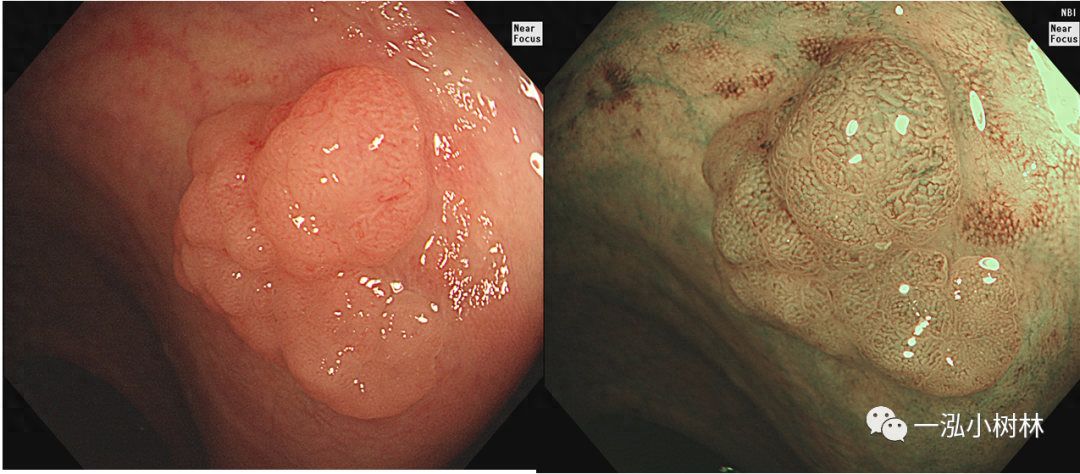

图3 结肠管状腺瘤(Pit Pattern IIIL型)